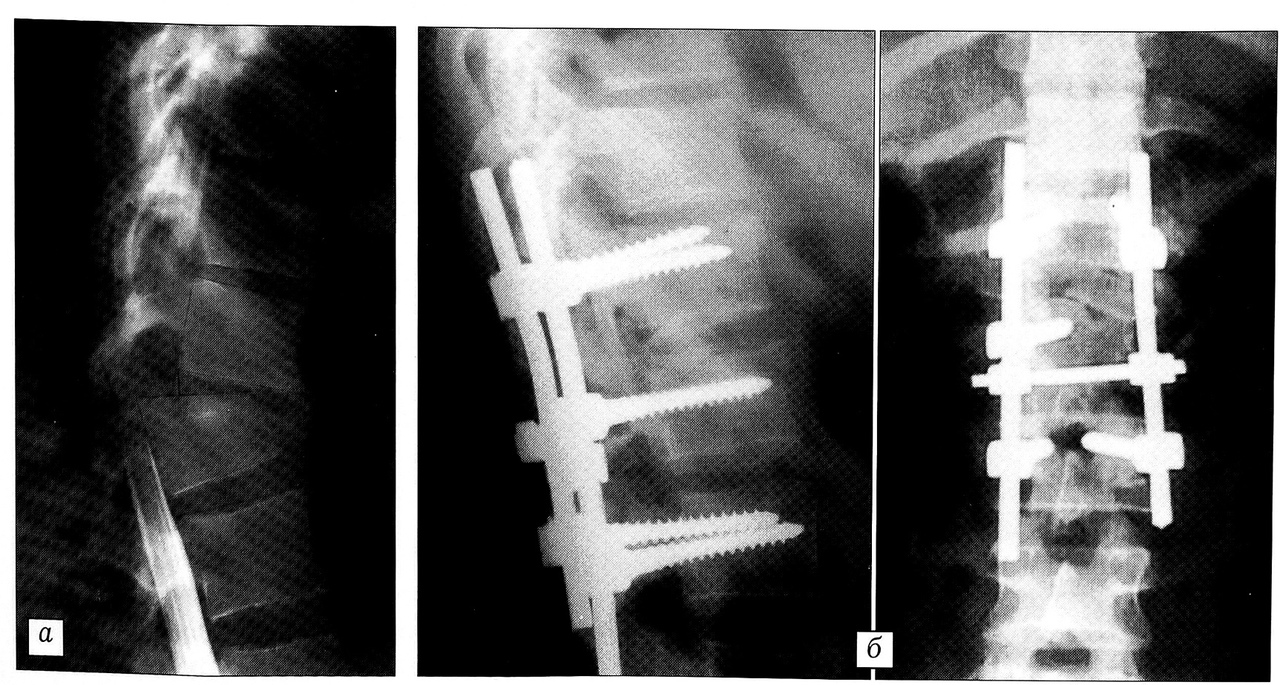

Для спондилодеза использовали различные аутотрансплантаты — из крыла подвздошной кости, остистых отростков, ребер, а также аллотрансплантаты (в одном случае). У 10 больных произведены фенестрация поврежденного диска и корпородез аутотрансплантатом из заднебокового доступа с использованием специального инструментария (рис. 3). В 2 случаях при переломе Тб позвонка выполнен корпородез заднебоковым доступом (костотрансверзэктомия). Задний и заднебоковой спондилодез произведен 45 больным.

Рис. 3. Больная 23 лет: a — переломовывих Т12, сложненный повреждением каудальных отделов спинного мозга (миелограмма в боковой проекции); б — произведены открытая репозиция, ревизия спинного мозга, фиксация системой CD, межтеловой спондилодез T12-L1 аутотрансплантатом из крыла под вздошной кости.